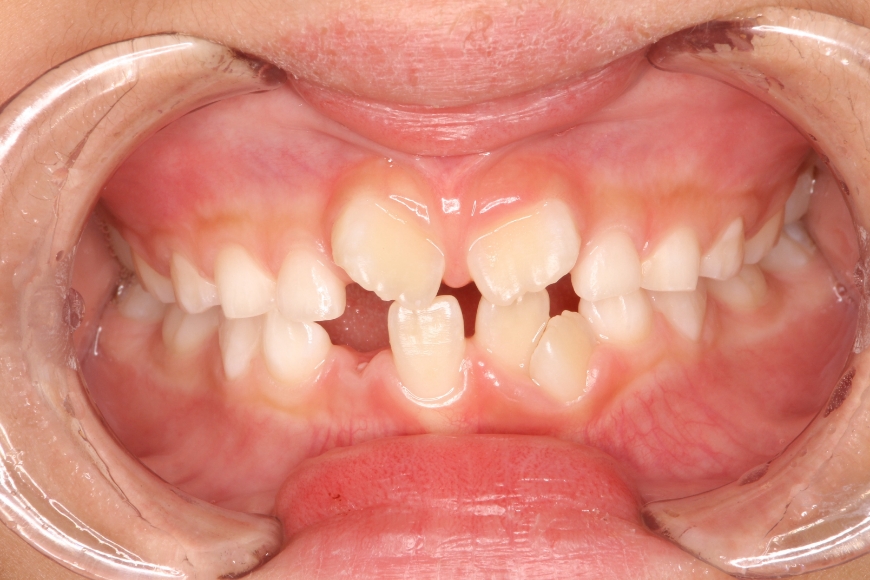

8歳男児 歯並びをきれいにしたい(保護者より)

治療前

治療後

治療内容 「がたがたの歯を治したい」と保護者と共に来院されました。

スペース不足による叢生(ガタガタの状態)と、前歯の見栄えが悪い状態でした。

床矯正装置にて2年程度歯列拡大を行い、永久歯の萌出誘導を行い、きれいな歯並びを獲得しました。

治療期間・回数 治療期間:約3年

通院回数:25~30回程度(成長段階に合わせた調整含む)

242,000

(調整料込、治療時の金額であり、時期や手法により異なる場合があります。)

副作用・リスク ・顎の成長後に後戻りが起こる可能性があります。

・予定より治療期間が長くなることがあります。

・2期治療(大人の矯正)に移行することがあります。